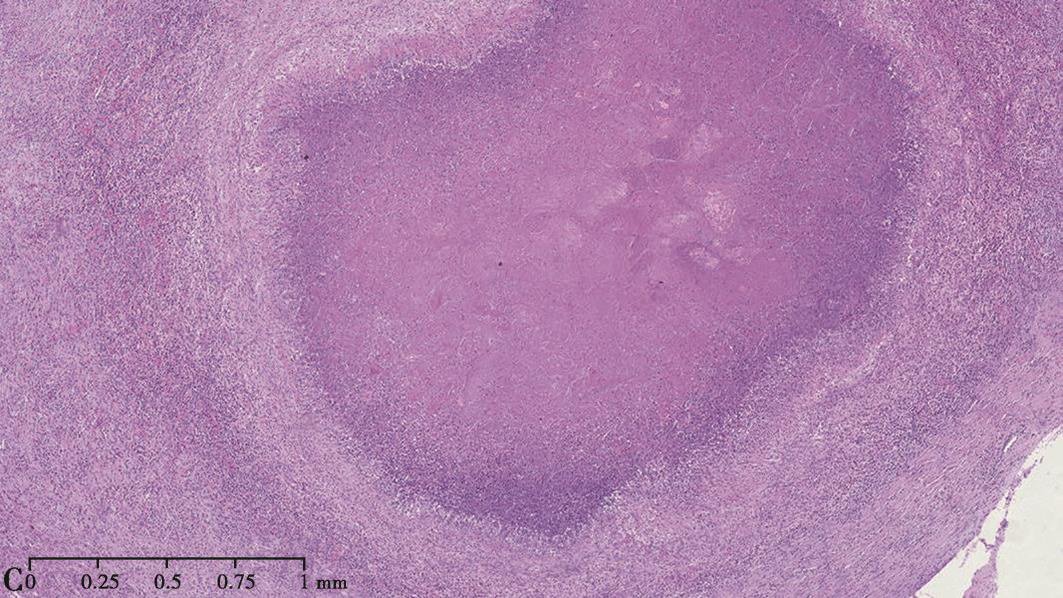

1小时条评论49岁女性,因间断发热3个月,双侧胸痛1个月余入院。胸部CT示双肺多发结节影、实变影和空洞影,多在胸膜下分布,有一定的游走性。外院肺穿刺病理示肺组织慢性炎症伴炎性渗出及坏死。外院曾先后予以多种广谱抗生素联合治疗,症状均无改善。该患者所患何病?如何治疗? ...